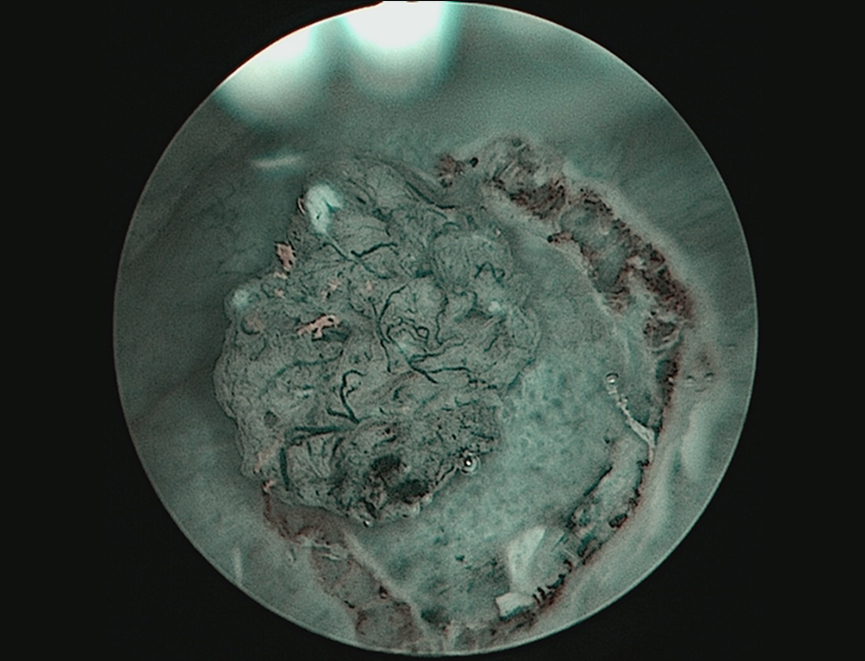

图2-aBT-ESD切除标本基底部病理(x40)

图2-b TURB切除标本基底部病理(x40)

图2.BT-ESD切除标本与TURB切除标本基底部病理比较

通过我们的研究,我们认为应用BT-ESD技术治疗肿瘤直径1~3 cm低危膀胱尿路上皮癌,有较好的安全性与可行性,而且肿瘤预后也可能优于TURB,其原因可能和肿瘤被完整切除并取出,减少了可能的残留或种植的风险[6];术中注射形成的水垫、清晰的层次,保证了切除深度在粘膜下层以下,降低了因经验不足,切除深度不够的可能[7]。而且,相比较TURB,BT-ESD技术能够减少严重并发症的发生率,特别当肿瘤位于膀胱侧壁或输尿管口附近时。此外,术后清晰详尽的病理(边缘有无肿瘤、粘膜固有层或肌层有无浸润)较TURB破碎、因烧灼焦痂无法辨识的病理,更能为如何决策后续治疗(是否行二次电切、是否行持续灌注)提供证据。(图2)